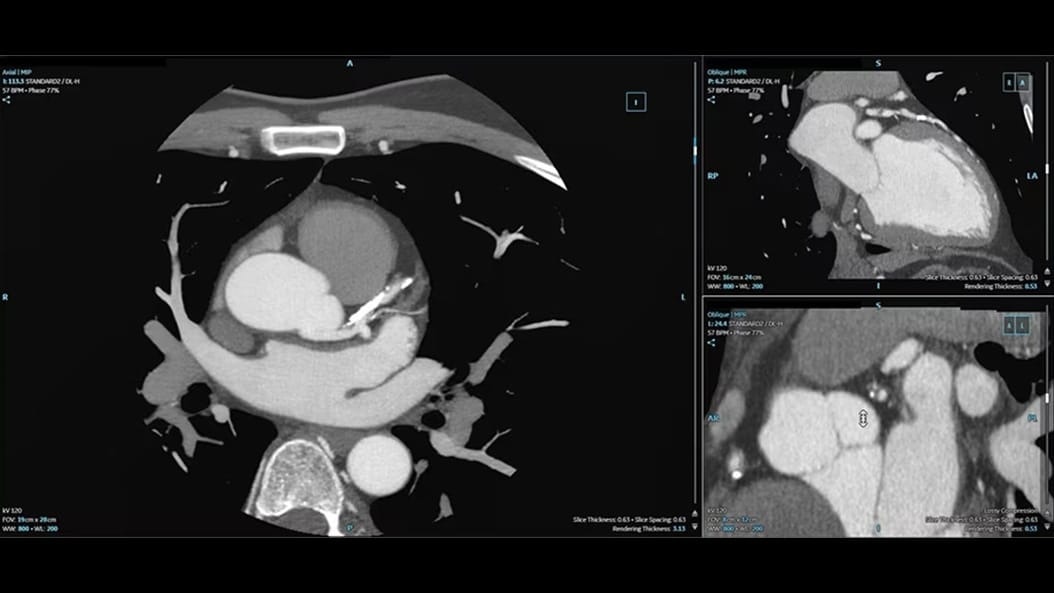

Expect exceptional results routinely—in a single beat

Complex CCTA becomes routine when advanced AI supports every image—streamlining and standardizing workflows even for challenging patients with unreliable ECG traces. See how Radiomed transformed its cardiac CT program to consistently deliver exceptional results.